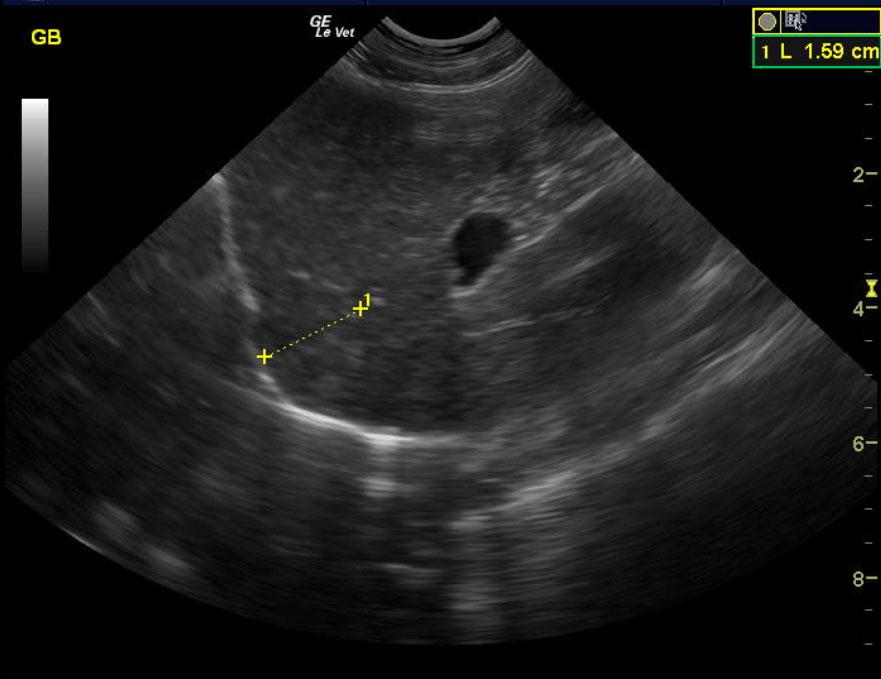

A 15-year-old MN DMH cat was presented for chronic diarrhea, hyperthyroid, dehydration, otitis externa, and periodontal disease. The CBC was markedly normal with blood chemistry revealing an elevated ALT (154,) elevated SAP (109,) hyperT4 (>10,). An IDEXX feline diarrhea panel was negative for virus, parasites, & bacteria.